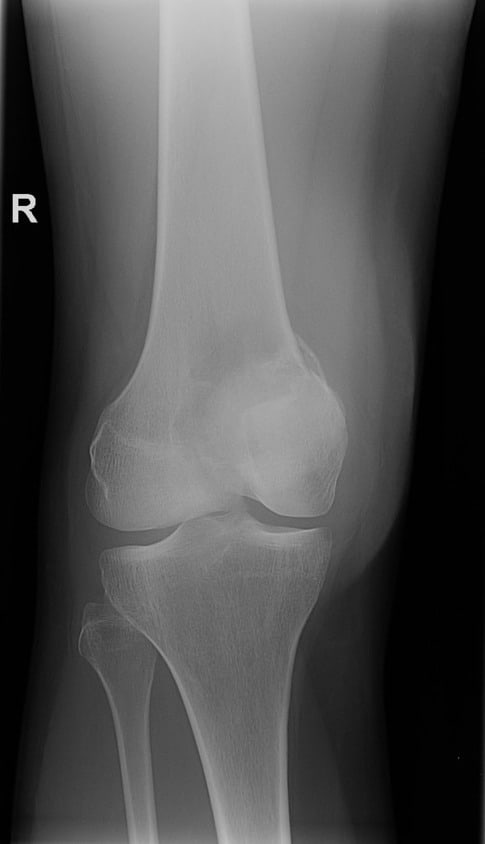

U tế bào khổng lồ

» Thông tin: Nữ giới – 31 tuổi.

» Lâm sàng: Đau khớp gối.